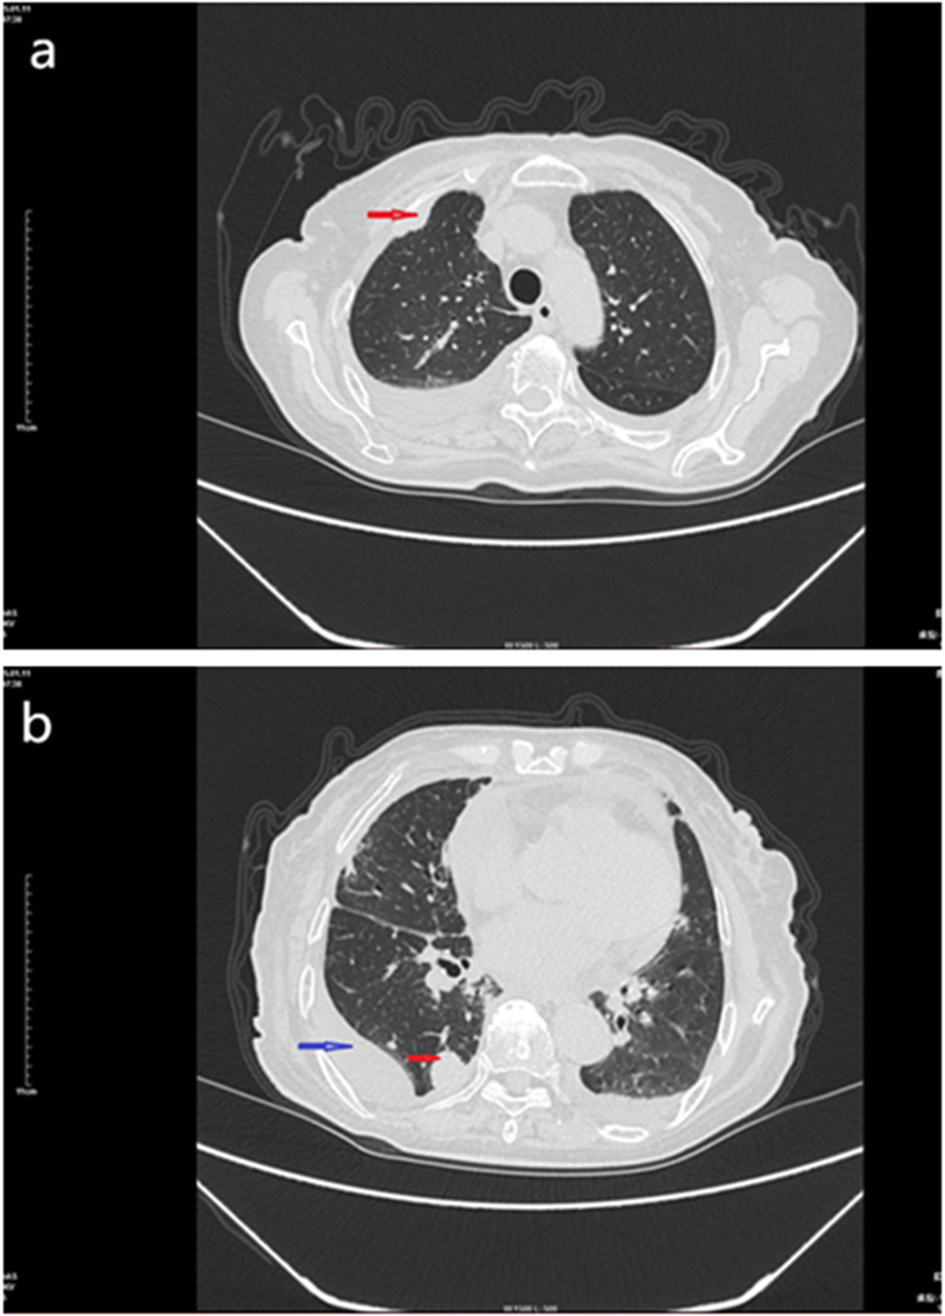

On January 11, 2025, enhanced chest CT (Figures 1a, b) revealed a mass in the lower lobe of the right lung, involving the right pulmonary hilum and right pleura, and multiple small nodules in both lungs with a small amount of pleural effusion. Mass in the left hilar lung. No significant tumors were found in other parts of the body.

Figure 1

CT scan of the chest mass, January 11, 2015. (a) Enhanced chest CT showing a soft tissue mass in the right lung pleura (red arrow). (b) Enhanced chest CT showing a mass in the right lung (red arrow) and pleural effusion (blue arrow).